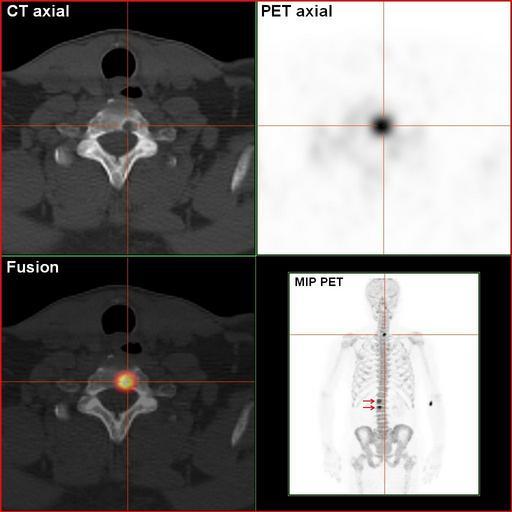

MAKE A MEME View Large Image RenalCancer-90MBq-F-18-Fluorid-PET-CT.jpg en Sodium-Fluoride-PET-Scan of a patient suffering from kidney disease with several bone matastases in the vertebral column This is the same patient as shown in the image RenalCancer-700MBq-HDP-Bone...

Keywords: RenalCancer-90MBq-F-18-Fluorid-PET-CT.jpg en Sodium-Fluoride-PET-Scan of a patient suffering from kidney disease with several bone matastases in the vertebral column This is the same patient as shown in the image RenalCancer-700MBq-HDP-BoneScinti-3hpi jpg The osteolytic metastasis in the neck is clearly visible de Natriumfluorid-PET/CT-Scan eines Patienten mit metastasiertem Nierenkarzinom Dies ist der selbe Patient wie im Bild RenalCancer-700MBq-HDP-BoneScinti-3hpi jpg Die osteolytische Knochenmetastase in der Halswirbelsäule ist klar dargestellt own Hg6996 2011-03-14 Mit freundlicher Genehmigung Südwestdeutsches PET-Zentrum Stuttgart am Diakonie-Klinikum Stuttgart Cc-zero Positron emission tomography